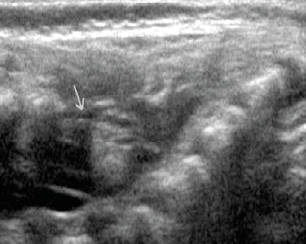

Lisa Bouma, MD; Magda Mendez, MD, FAAP; Sergey Prokhorov, MD; Apeksha Sathyaprasad, MD

A 2-month-old boy was referred to a neurology clinic for a superficial strawberry hemangioma over his lower back.